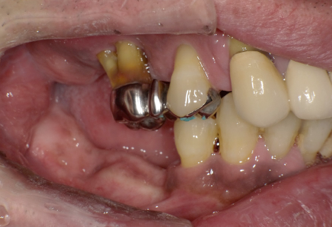

中途半端に悪い歯を残すと、後々治療が大変になるので思い切ってすべての歯を抜歯します

術直後の写真です

オールオン6本のインプラントをいれました

初期固定もよかったので即時荷重をおこなっています